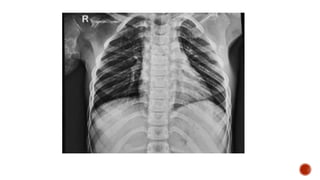

Frontal chest radiograph shows few ill defined patchy opacities in both the lung

fields, few of them showing cavitatory changes. TCC seen in situ.

Compared to the previous radiograph there is reduction in the number of opacities

with cavitatory changes.

 Malignancy:

 Squamous cell carcinoma of the lung

 Metastasis :

 squamous cell ca

 adenoca from GIT/breast

 sarcoma

 cervical carcinoma

 urothelial carcinoma of the bladder

 Infection :

 Septic embolism

 Pulmonary tuberculosis

 Abscess

 Post pneumonic pneumatocele

 Necrotizing pneumonia

 Distribution :

 Peripheral

 Lower lobe predominance

 Multiple

 Bilateral

 Varying stages of cavitation

 Feeding vessel sign